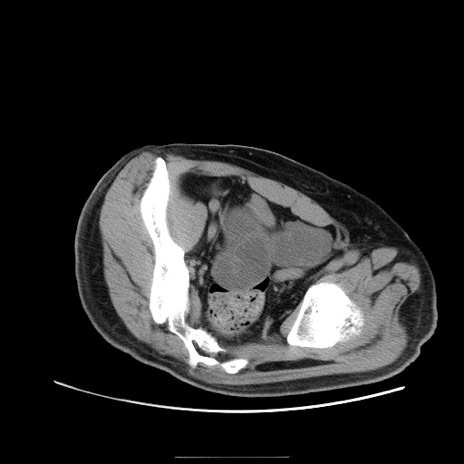

冠状断像

【症例】50歳代男性

【主訴】腹痛

【現病歴】AVMからの被殻出血のため回復期リハ病棟入院中。 本日午後3時頃急に下腹部痛が出現した。

【既往歴】AVM、被殻出血、虫垂炎、高血圧

【身体所見】意識晴明、左半身不全麻痺、会話の理解は良好、36.5°C、腹部:膨隆、全体に板状硬、下腹部正中に圧痛点あり、反跳痛-、筋性防御不明、右下腹部にope scar

【データ】WBC 9400、CRP 0.06